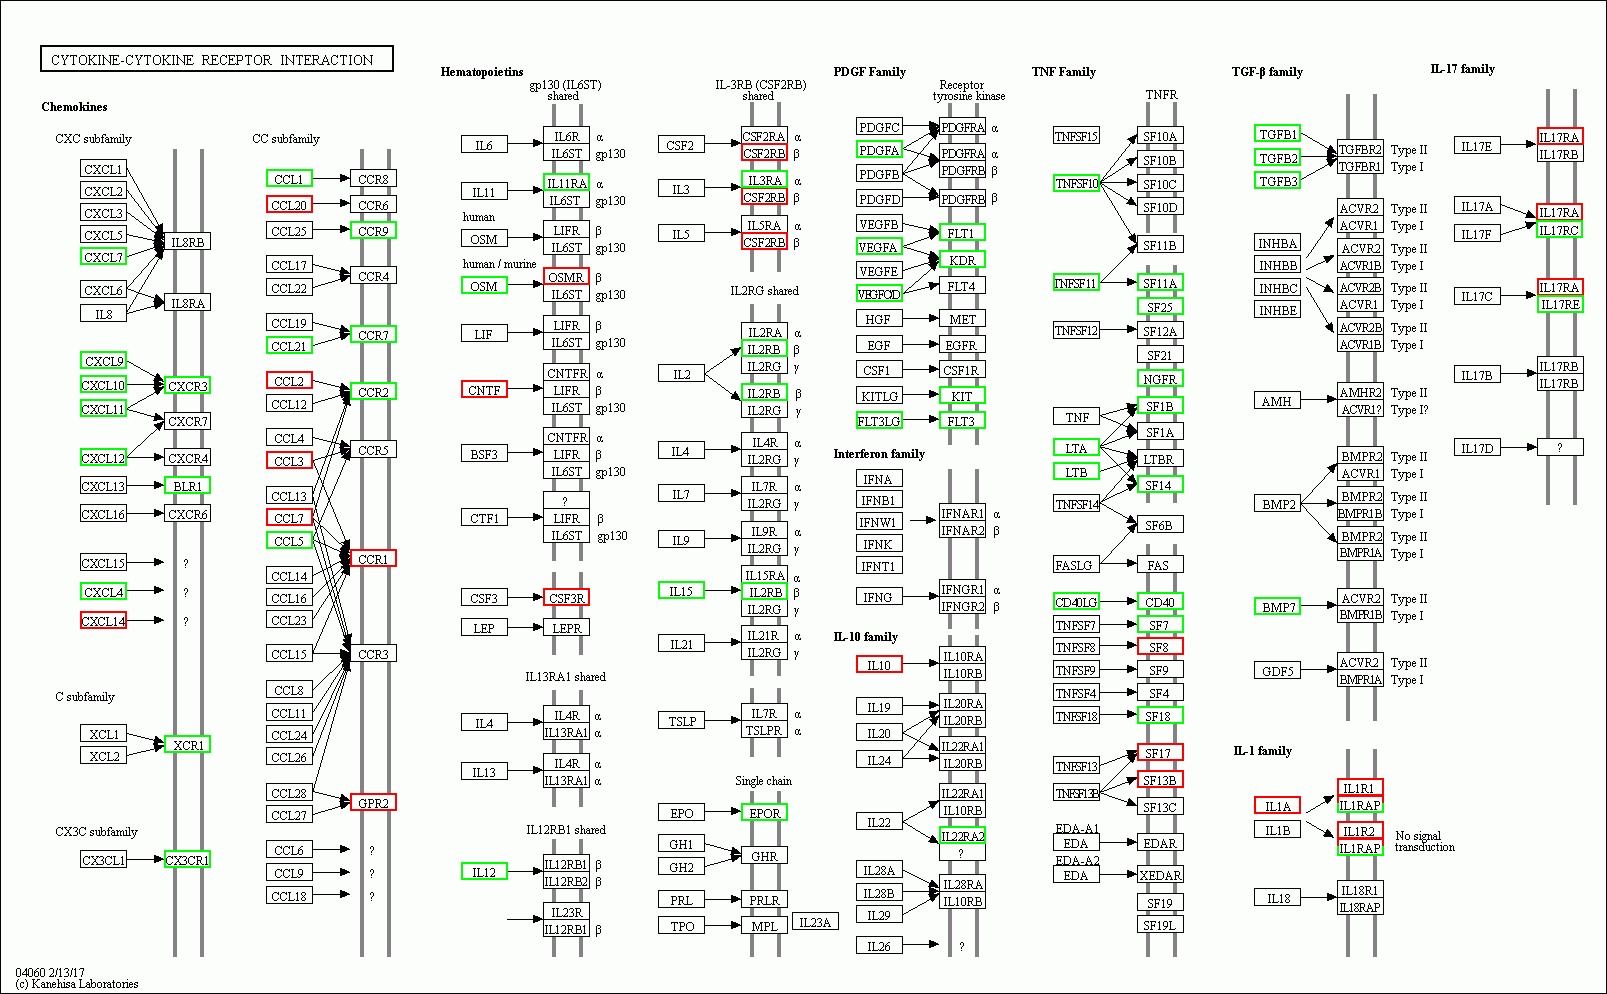

2 结果48 h各组病理结果,对照组脾组织结构正常(见图 1A )。脓毒症组脾组织见白髓结构破坏,红白髓交界模糊,多量组织细胞浸润,红髓充血(见图 1B)。差异mRNA的Volcano-plot分布图(见图 2)。相比于对照组,24 h时脓毒症组脾组织mRNA表达上调的有1 030个,下调的有935个[5];48 h组表达上调的有1 354个,下调的有1 763个。差异mRNA的聚类情况(见图 3)。GO功能分类结果(见图 4)。脓毒症大鼠脾组织部分通路相关基因表达情况(见图 5、6):脓毒症大鼠24 h,48 h脾组织关于细胞因子及其受体相互作用通路相关基因的分布图(见图 7,图 8)。脓毒症大鼠24 h,48 h脾组织关于细胞凋亡相关通路的基因分布图(见图 9,图 10)。

| 图 8 脓毒症大鼠48 h组 |

(1)细胞与其受体相互作用信号通路相关的基因表达上调数明显减少,部分甚至转为下调。从图 7、8可以看出脓毒症大鼠24 h脾组织mRNA表达上调,而48 h转为下调的有2个:CXCL10、CCL1;从上调转为正常表达的有22个:CXCL16、CNTFR、IL9R、IL23A、HGF、IFNB1、IL22、PDGFRA、IL28RA、TNFSF9、SF12A、SF9、SF19L、IL1β、ACVR1B、CXCR7、CXCR4、IL6、LIF、CSF3、IL6ST、CCL4。从正常表达转为下调的有30个:CXCL9、CXCL11、CXCL4、CCL21、CCR7、OSM、IL12、IL11RA、IL15、IL3RA、IL2RB、EPOR、PDGFA、VEGFA、VEGFOD、FLT1、KDR、KIT、FLT3、TNFSF10、SF11A、NGFR、SF14、CD40、TGFB1、TGFB2、TGFB3、IL17RC、IL17RE、BLR1。而从表达下调转为上调的仅一个:IL17RA,从下调转为正常表达的仅2个:FASLG、TNFSF8,从正常表达转为上调的有10个:CCR1、GPR2、CNTF、CSF3R、SF8、SF17、SF13B、IL1A、IL1R1、IL1R2。从中可以看出脓毒症早期细胞因子与其受体相关基因表达以上调为主,脓毒症晚期则相反,部分基因转为下调,部分基因转为正常表达,多数正常表达基因在晚期出现表达下调符合脓毒症早期过度炎症反应、晚期免疫抑制的观点。